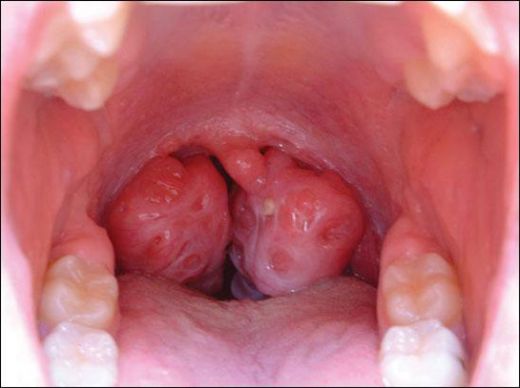

Cevap yazSol Bademcik Çürümeleri Belirtileri

Sol bademcik çürümeleri genellikle yutkunma zorluğu, boğazda tahriş, ağrı ve yüksek ateş gibi belirtilerle kendini gösterir. Bu durum, bademcik iltihabı veya diğer enfeksiyonların bir sonucu olabilir.

Alpartur, yaşadığın bu durum gerçekten de rahatsız edici olabilir. Boğazdaki ağrı ve yutkunma güçlüğü, günlük yaşamı olumsuz etkileyebilir. Beyaz lekelerin varlığı, enfeksiyon belirtilerine işaret edebilir ve bu nedenle doktora başvurman çok önemli bir adım.

Dikkat Edilmesi Gerekenler

Tek taraflı bademcik şişmesi, bazen daha ciddi durumların bir belirtisi olabileceğinden, doktorun önerilerini dikkatle takip etmekte fayda var. Özellikle ateş, şiddetli ağrı veya nefes alma zorluğu gibi belirtiler varsa, derhal sağlık kuruluşuna başvurmak gerekebilir.